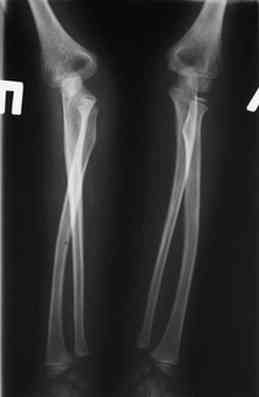

Иллюстрация к лечению застарелого повреждения Монтеджиа

Пациентка клиники детской травматологии ЦИТО

На рентненграмме видна деформация локтевой кости на границе верхней и средней трети. Ведь там был перелом.

Уважаемые коллеги, кто-нибудь еще видит здесь застарелое повреждение Монтеджи? Может мне показалось?